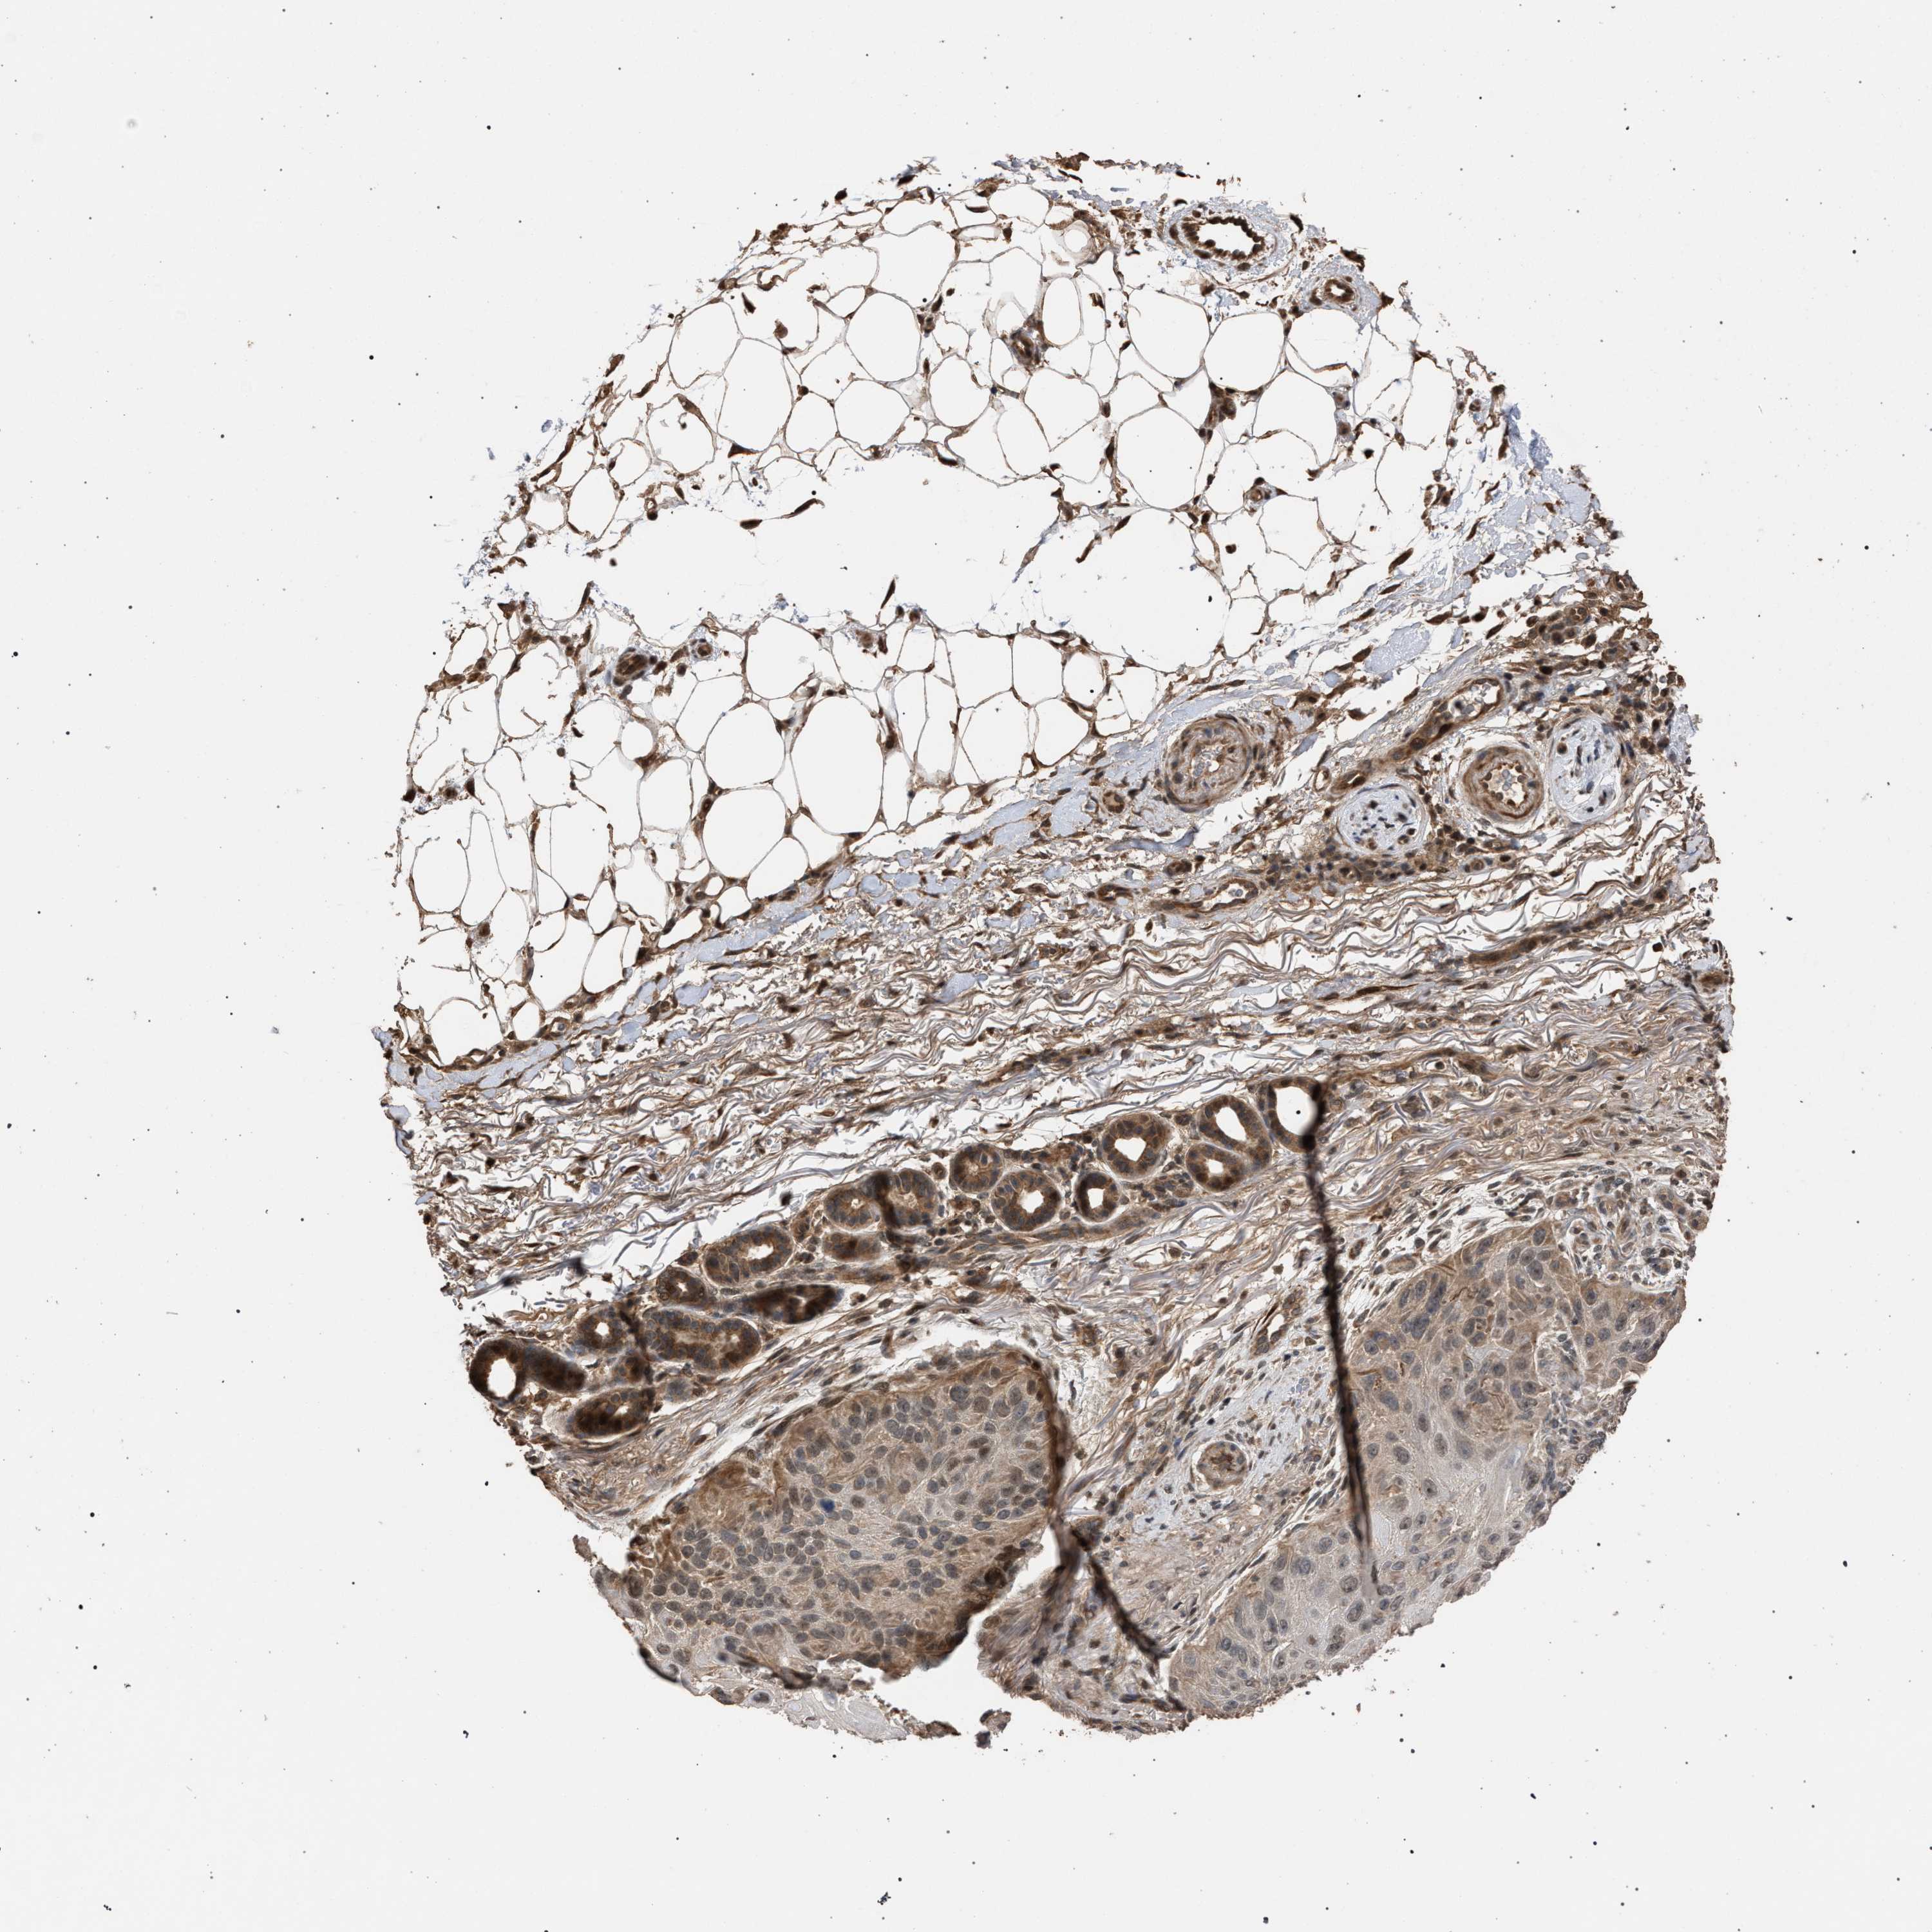

SKIN CANCER - Protein expressioni

A mouse-over function shows sample information and annotation data. Click on an image to view it in a full screen mode. Samples can be filtered based on level of antibody staining by selecting one or several of the following categories: high, medium, low and not detected. The assay and annotation is described here.

Antibody staining in the annotated cell types in the current human tissue is reported as not detected, low, medium, or high, based on conventional immunohistochemistry profiling in selected tissues. This score is based on the combination of the staining intensity and fraction of stained cells.

Each image is clickable and will lead to virtual microscopy that enables deeper exploration of all samples and also displays staining intensity scores, fraction scores and subcellular localization as well as patient and tissue information for each sample.

Antibody HPA021547

Staining

High

Medium

Low

Not detected

Intensity

Strong

Moderate

Weak

Negative

Quantity

>75%

75%-25%

<25%

None

Location

Nuclear

Cytoplasmic/membranous

Cytoplasmic/membranous,nuclear

Basal cell carcinoma

Squamous cell carcinoma, NOS

Squamous cell carcinoma, metastatic, NOS